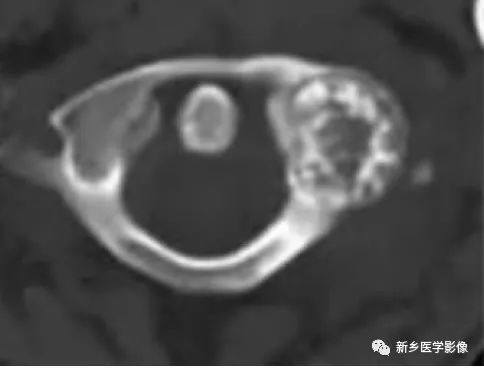

左股骨大转子骨样骨瘤1例X线CT

影像表现:

骨样骨瘤的影像学表现具有特征性,其典型的表现为:

瘤巢所在部位的骨质破坏及周围不同程度的骨质硬化,还可伴有骨膜反应、周围软组织或相邻关节的肿胀。

骨样骨瘤的肿瘤区称为“瘤巢”

—圆形或卵圆形,直径<2cm

—富血管的结缔组织基质,内部含有不等量的骨样组织或骨组织

—CT/平片:低密度,但内部的骨组织表现高密度

—增强扫描时,瘤巢可出现不同程度的强化

CT/平片上,“瘤巢”周围多出现反应性骨质增生硬化:松质骨增生硬化或骨膜反应

骨样骨瘤是一种较常见的良性骨肿瘤,瘤巢的确定是影像诊断骨样骨瘤的关键:

CT是目前发现瘤巢的最佳方法;